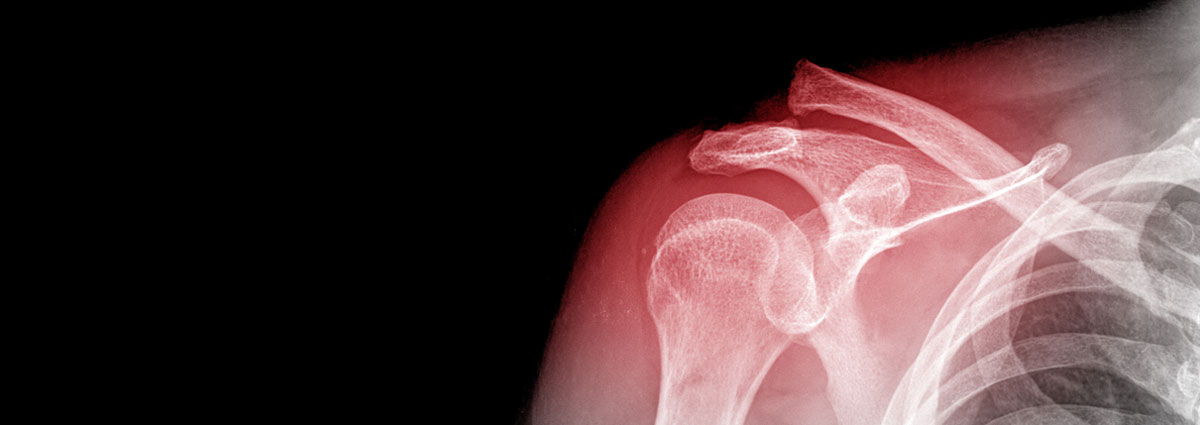

The shoulder is the joint that connects the torso to the arm and is made up of three bones: the scapula or shoulder blade, clavicle, and humerus. Surrounded by cartilage that allows for smooth, painless movement, the shoulder is divided into two joint cavities: the subacromial space (where the rotator cuff tendons are located, whose function is to stabilise the shoulder joint when raising the arm and performing flexion and external rotation of the arm) and the glenohumeral joint (where the ligaments are located that act as reinforcement and provide stability to the shoulder, preventing joint dislocation).

Fractures are injuries caused by high-impact trauma that results in a break in the bone. Fractures in the shoulder joint can occur in any of the three bones in the joint:

- Clavicle fracture: these are usually caused by a fall onto the shoulder, which transmits the deforming force to the clavicle, causing it to fracture.

- Scapula or shoulder blade fracture: these are rare and usually occur in high-energy trauma affecting the shoulders, chest and spine.

- Humeral head fracture: these also involve high-energy trauma. This injury occurs more frequently in elderly people due to decreased bone density.